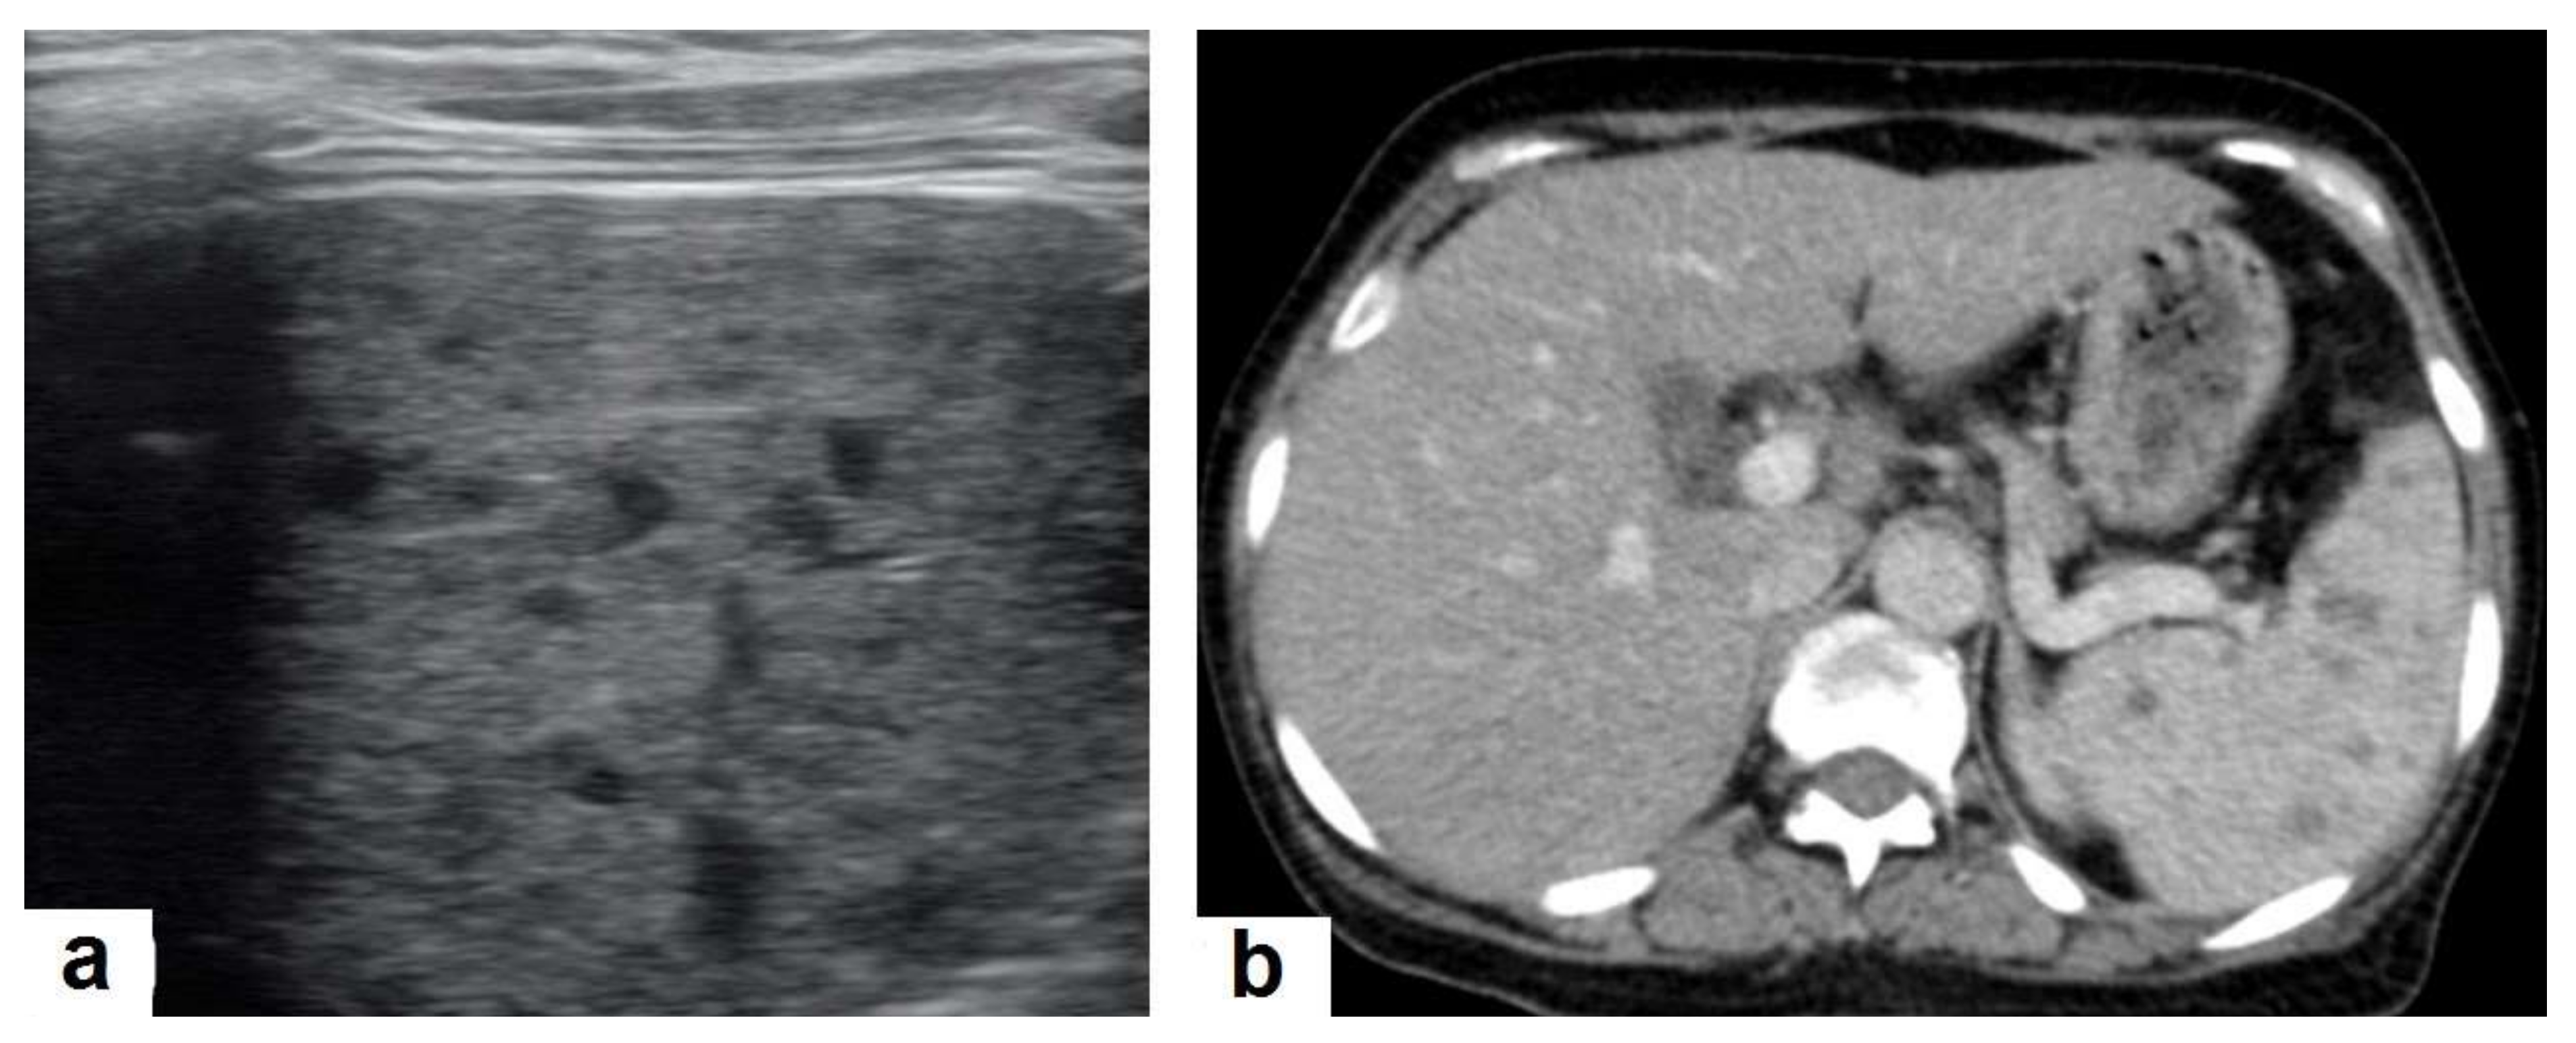

Figure 7. Miliary TB in an adult female with fatigue and loss of appetite. (a) Splenic ultrasonography shows multiple small hypoechoic granulomas with random distribution in the spleen. (b) Axial abdominal CT shows small non-enhancing granulomas with random distribution in the spleen clearly seen during the portal venous phase with multiple enlarged lymph nodes around the portal vein.

• Miliary TB (Figure 6 and Figure 7) appears as innumerable small (1–3 mm) granulomas with random distribution in the lungs and other organs with a predominance to the lung bases due to the gravity-dependent high blood flow. It occurs due to the hematogenous dissemination of mycobacterium tuberculosis bacilli, especially in immunocompromised patients and children [1,13]. Miliary TB is a significant differential diagnosis of pulmonary metastasis from thyroid cancer or others, even in children [19].